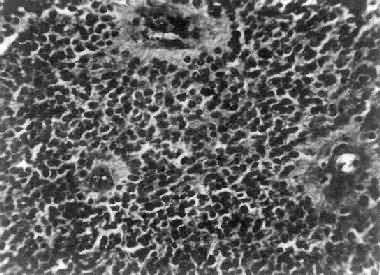

图16-25 室管膜

细胞为圆形或卵圆形,核染色质丰富,胞浆少,可见有细长的胞浆突起与血管相连,呈放射关,形成假菊形团